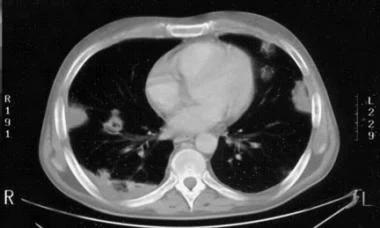

CT对免疫力低下非特异性浸润患者的早期诊断具有一定作用。CT扫描可观察曲霉菌患者的晕征。一项研究发现,在235例侵袭性曲霉菌感染的患者中,多达61%的患者出现晕征。

图2 侵袭性曲霉菌感染患者的CT扫描,示多处肺部病变。左肺空洞病变显示磨玻璃晕征。

图3 肺曲霉菌感染的CT扫描示多处基于胸膜的病变和肺实变。

由于肺曲霉菌感染的病死率高,应当对肺部感染提示曲霉病风险的患者,尽早进行CT扫描。在血液恶性肿瘤患者中,有几种非特异性表现以区分毛霉菌病与其他感染,尤其是曲霉菌。